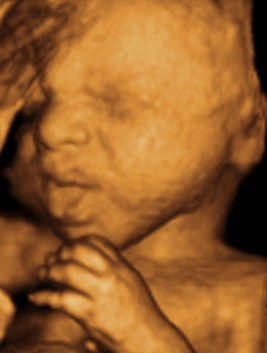

Kan da lige sætte et par billeder ind fra i mandags, hvor jeg var 27+5 uger henne, så du kan se kvaliteten

Vedhæftede fotos (klik for at se i fuld størrelse)